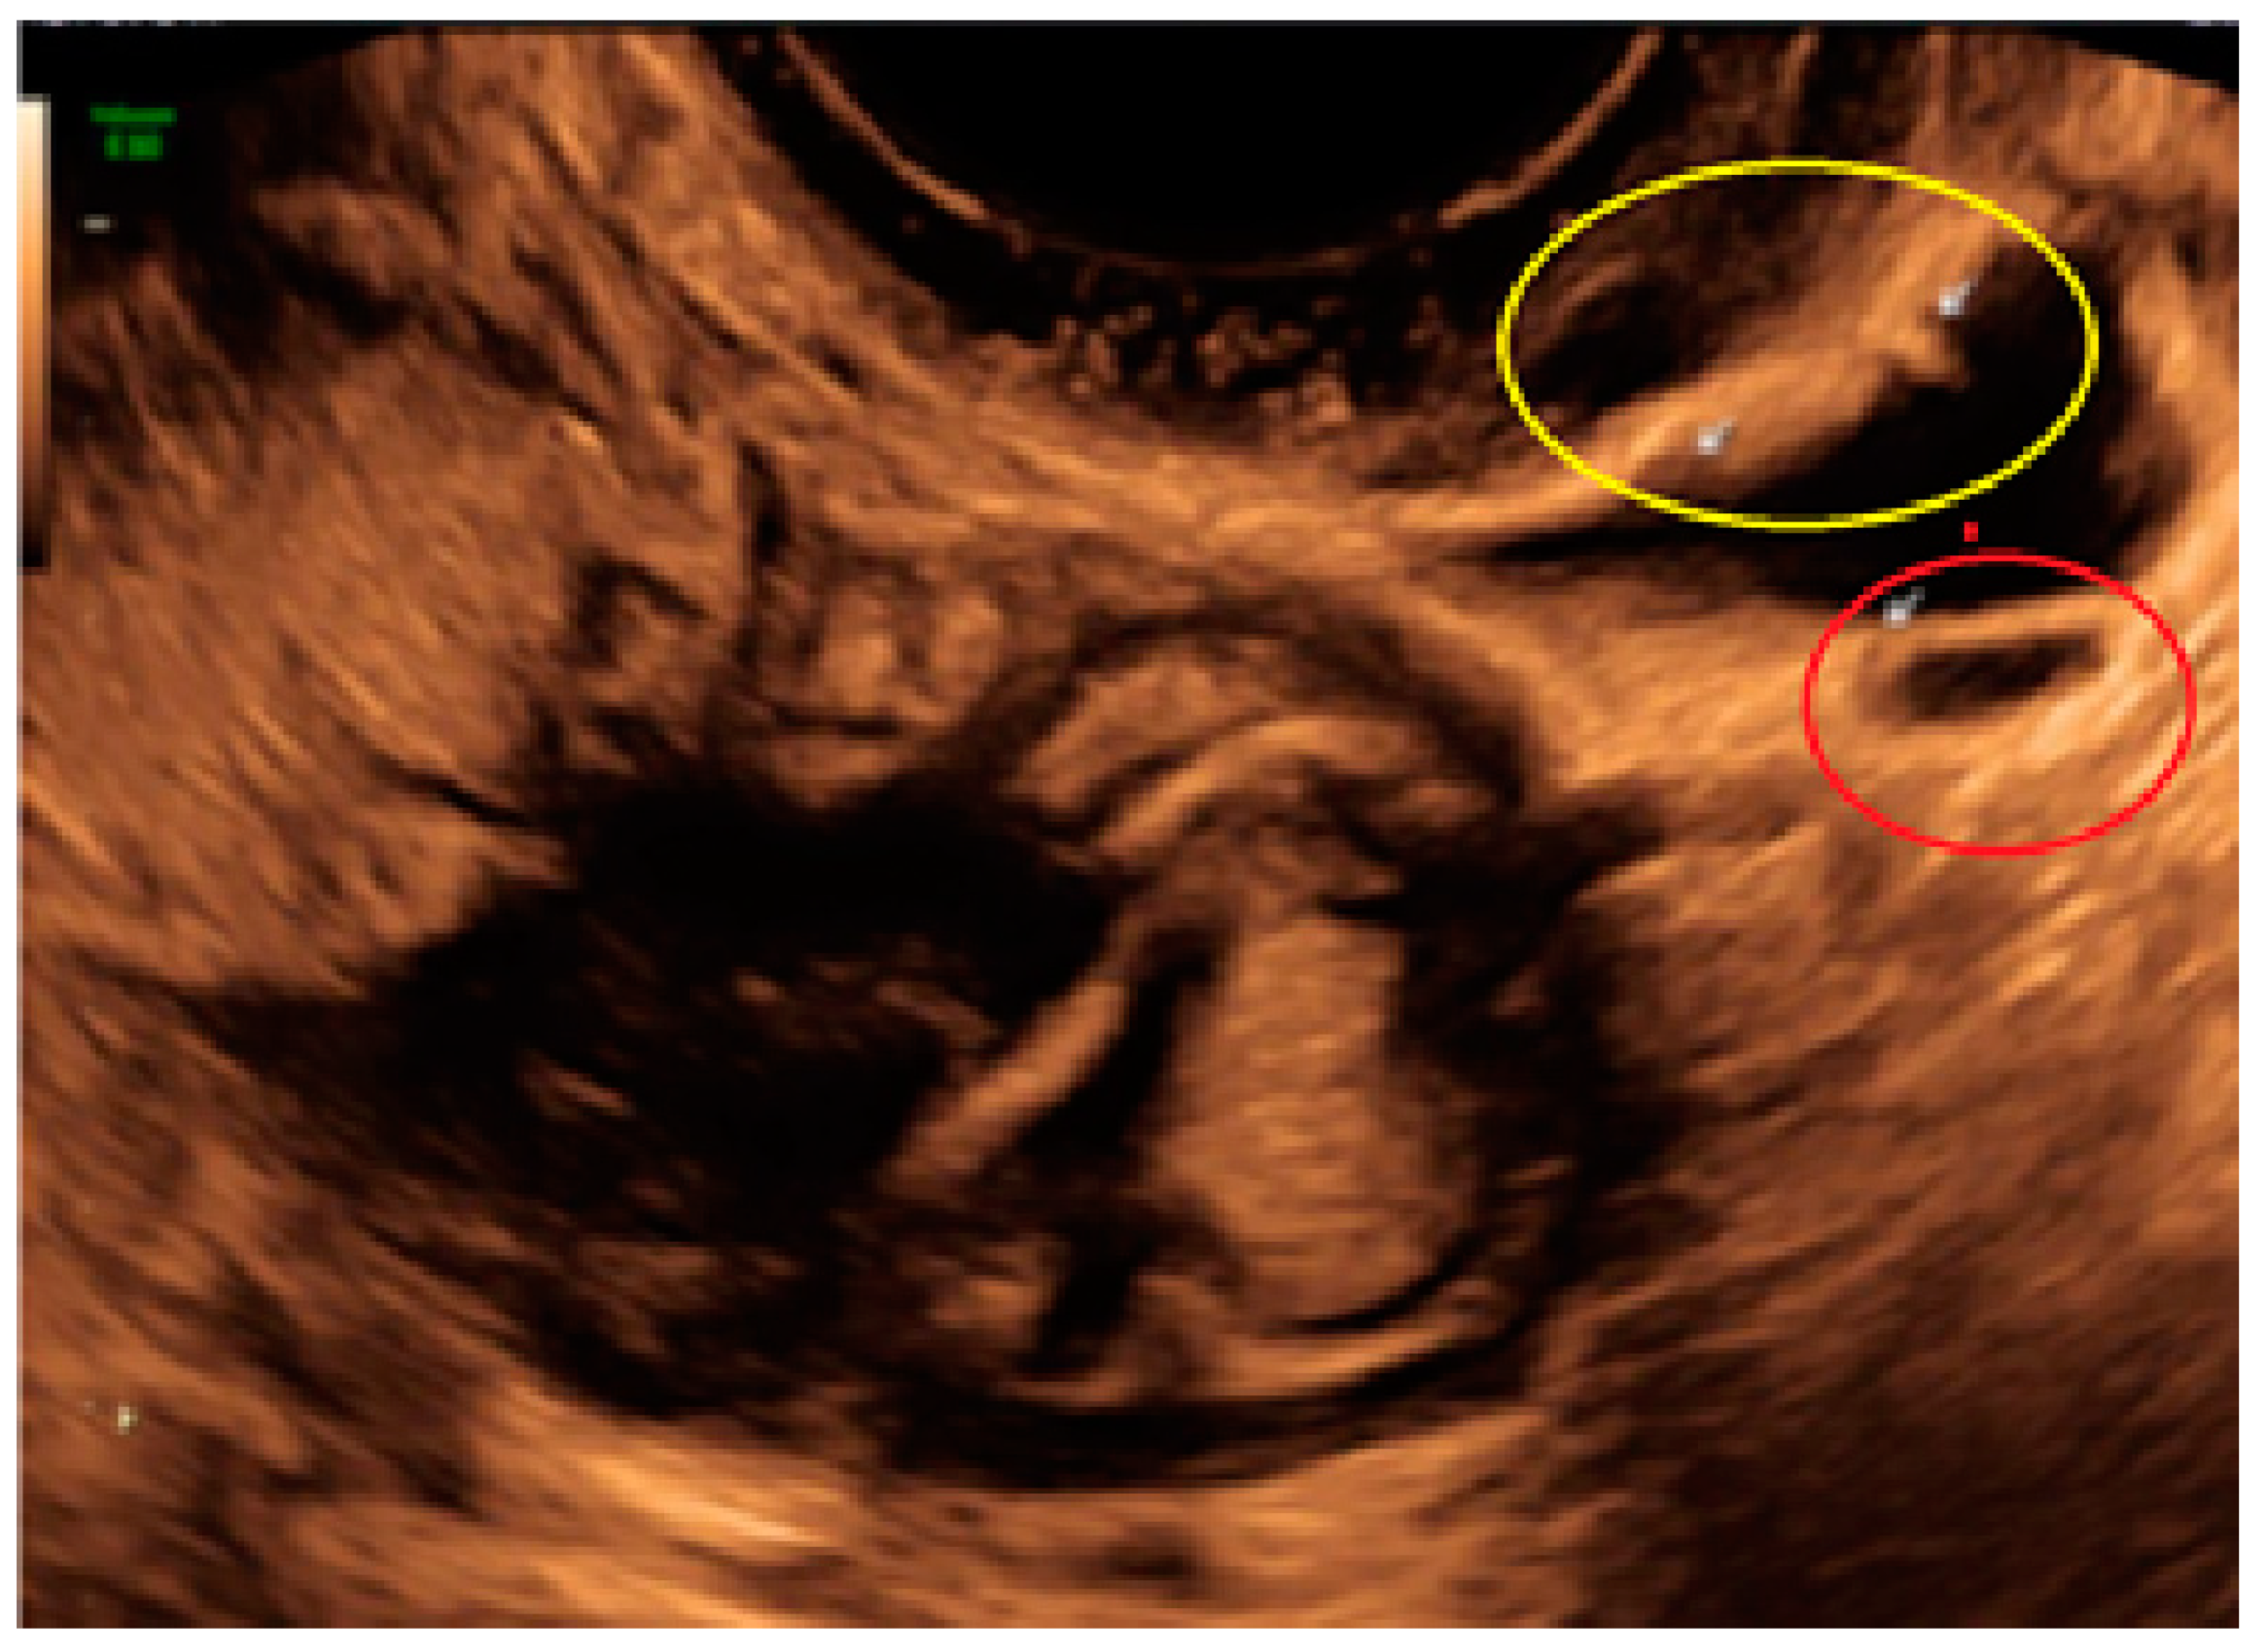

- The lesion may be convex, protruding from the peritoneal surface into the peritoneal cavity (we called this “bulging”), or it may appear as a concave defect in the peritoneum (we called this a “pocket”).

3.2. Cystic Multiple Separate Lesions

3.3. Cystic Lesions Arranged in a Cluster